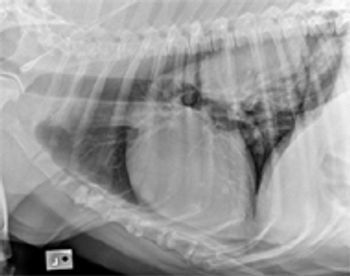

One of the subtleties of interpreting abdominal radiographs is peritoneal detail.